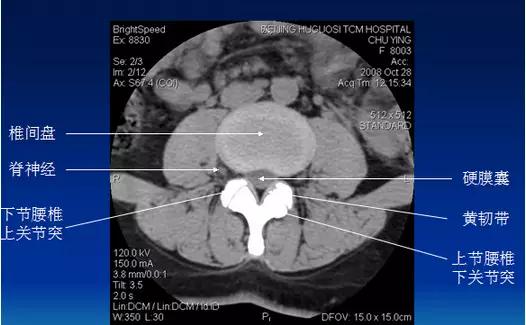

常规腰椎CT扫描层面

常规腰椎CT扫描L3-S1段,分为

(1)椎体层面(骨窗):观察椎体、附件骨质。

(2)椎间盘层面(软组织窗):观察椎间盘、硬膜囊、神经根、韧带等软组织。